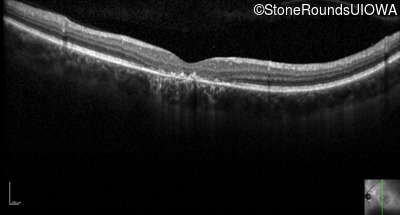

Optical Coherence Tomography - Right - 20/60 sc

Exemplar / OCT Stack